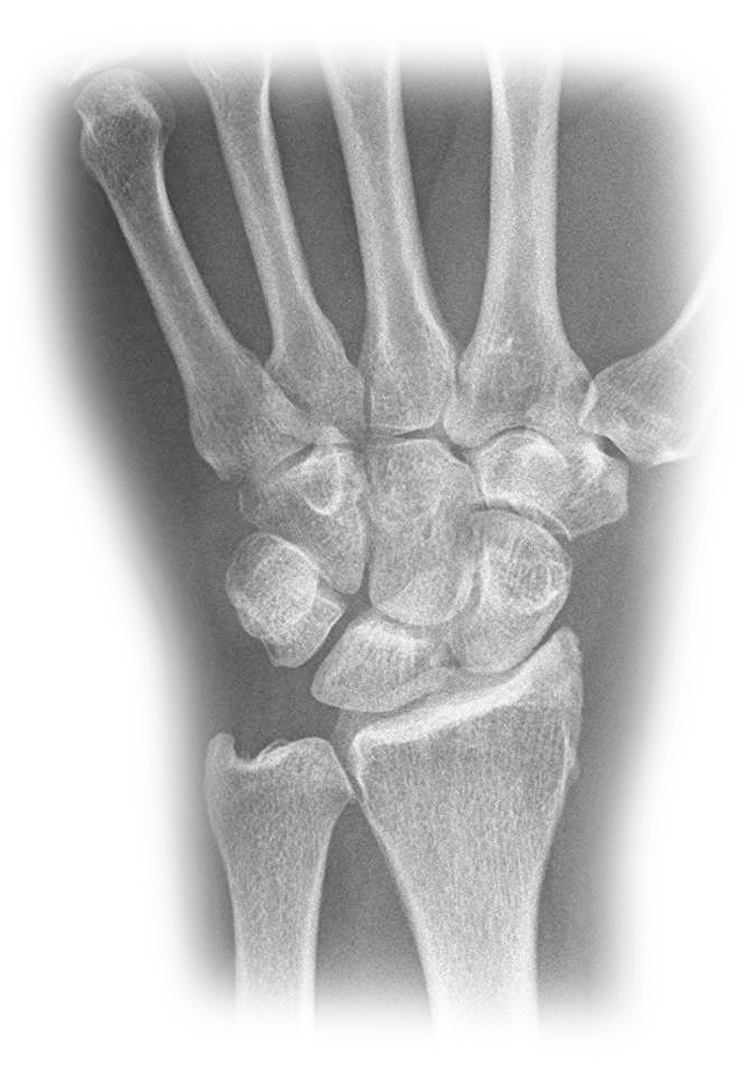

Handgelenk

Verletzungen und Erkrankungen des Handgelenkes

Welche Erkrankungen können wir in unserem Chirurgie Centrum mit der Arthroskopie am Handgelenk behandeln?

• Entfernung freier Gelenkkörper (Gelenkmaus)

• mehrfach operiertes Überbein (Ganglion)

• Schleimhautentzündungen (Synovitis)

• Verletzungen des Discus ulnaris und von Bändern

• Knorpelschäden (Arthrose)